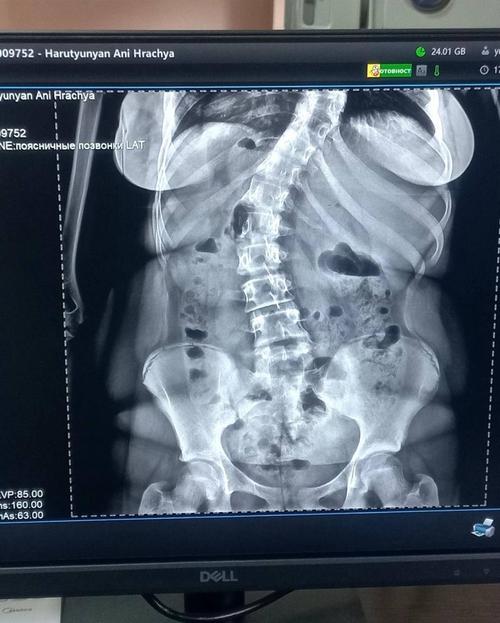

Dear supporters, we had very little time to secure a life saving surgery for Ani. Although we were not able to raise the full required amount, Ani’s family managed to gather the funds from various sources. Ani has already undergone a complex spinal surgery and is now in the recovery phase, but she still needs our support.

We would like to remind you that due to spinal deformity and the complications it causes, Ani was at risk of losing her ability to walk and move independently.